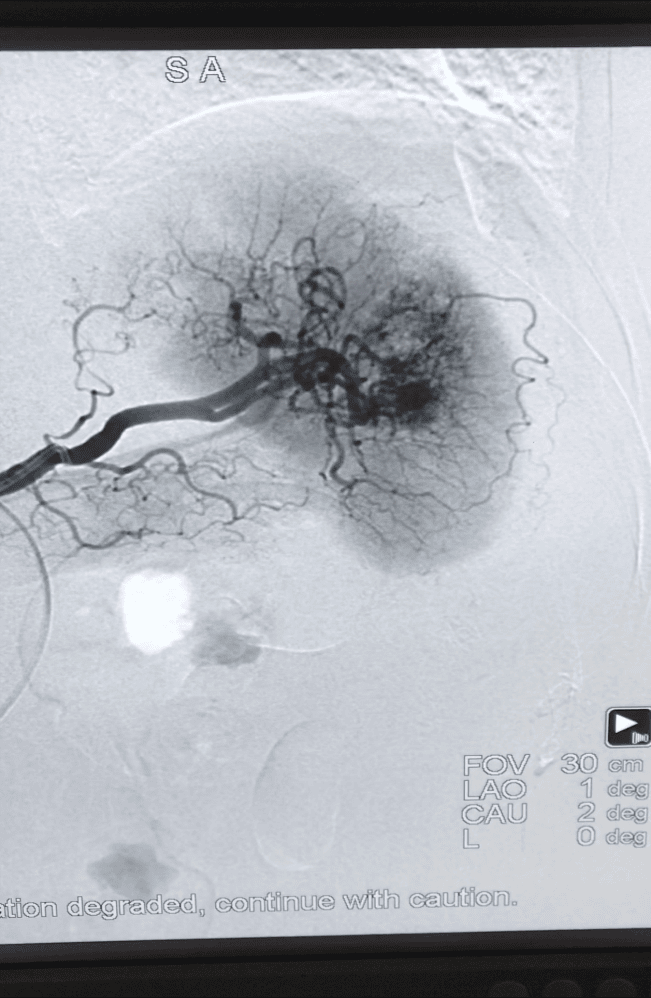

(脾脏破裂出血介入治疗前后造影对比)